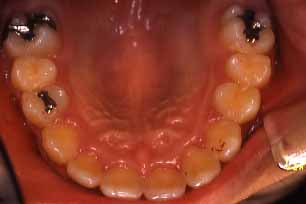

上顎

(ミラー像)